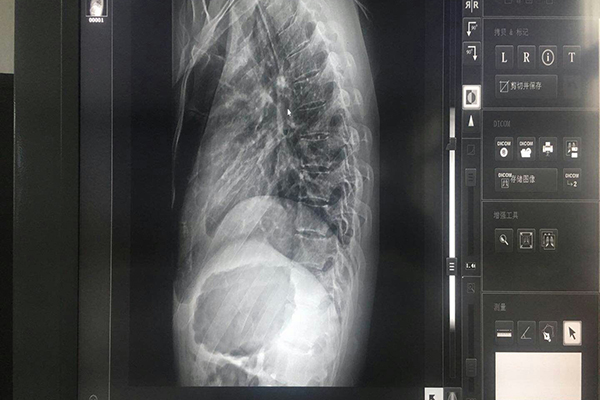

灰階監(jiān)視器全系列具備高性價比的臨床復查顯示器,能為用戶提供DICOM Park 14校準能力顯示。適用于MRI、CT、DSA、CR/DR、PASS醫(yī)生工作站、三維影像醫(yī)療等圖像顯示。符合DICOM標準的顯示性能,具臨床復查應用價值,在整個醫(yī)院內安裝高性能多用途的臨床復查顯示器,是解決醫(yī)院避免采購高昂器械的解決方案。

彩色顯示器和沒有DICOM顯示函數校準的黑白顯示器,無法很清楚的顯示5%及95%這兩個小方塊。若有病灶正好處于此處的灰階位置時,很容易漏診斷 。在放射學的診斷中,這種灰度差異(組織密度小差異性),有可能對早期病灶的診斷有很大的幫助。